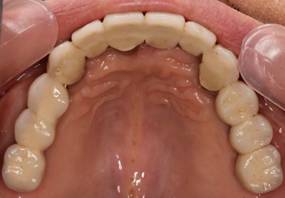

上顎

上部構造装着後6年。ハイブリッドレジンを使用したため、少し艶がなくなってきました。上部構造の材料には金属、ハイブリッドレジン、セラミックなどがあります。セラミックはきれいですが欠けやすいため、最近はフルジルコニアを使っています。

上顎 少しすり減ってきました。